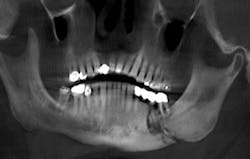

The presence of exposed bone may be subtle and may at first appear as a fistula or periodontal defect when probing, or granulation tissue covering over unhealed exposed bone.3 In reviewing the database from the University of Miami, 29% of cases of exposed bone develop spontaneously without any initiating insult to the alveolar bone, and 61.6% are initiated by extraction. Dental implant surgery accounts for 2.2%, bone biopsy 1.1%, and periapical surgery is an initiating event in only 0.5% of cases.3 Affected alveolar bone is often seen by observing sclerosis of the lamina dura in a radiograph or radiographic identification of a more diffuse sclerosis in the alveolar bone.3